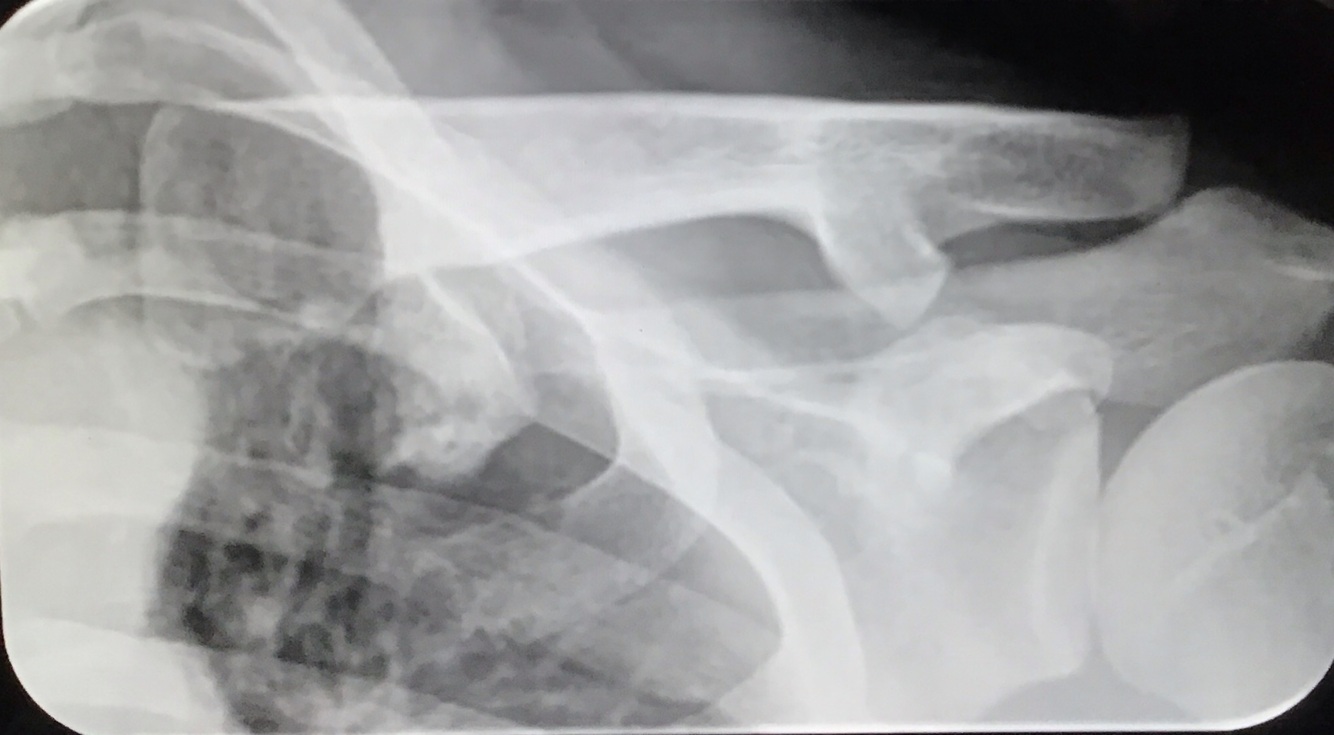

Qual a melhor incidência radiográfica pra avaliar LAC?

A

Zanca

angulação cranial de 10 a 15°